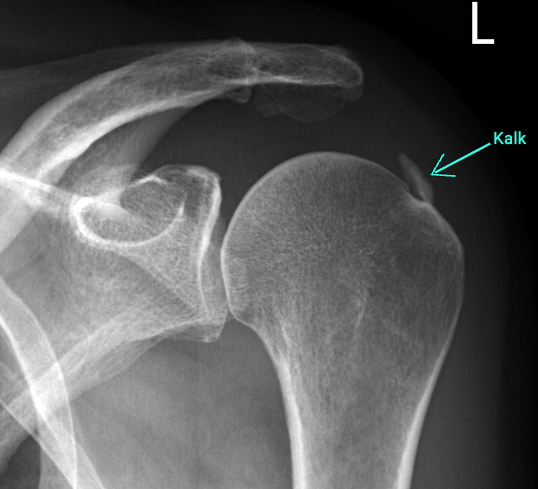

Calcified shoulder (tendinitis calcarea)

Calcific shoulder, medically known as tendinitis calcarea, is a painful disease of the shoulder in which calcium deposits form in the tendons of the rotator cuff. These deposits usually develop gradually and can go unnoticed for years - until they suddenly cause severe pain and restricted movement.

Typical symptoms are stabbing pains that occur mainly at night or during certain movements, such as lifting the arm. In acute phases, the pain can be so severe that everyday activities are hardly possible. Calcified shoulder can be easily diagnosed with an X-ray.